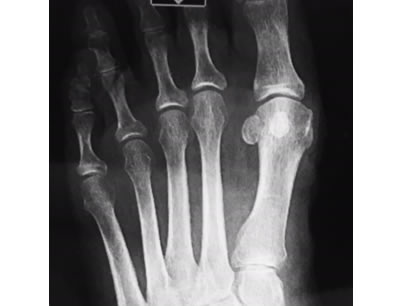

Non Arthritic Flatfoot Deformity

Correction of Deformity with Tendon Augmentation/transfer and Bone Grafting